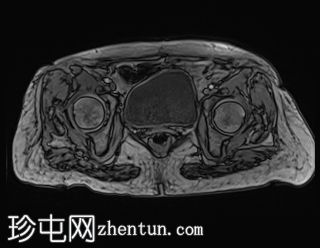

轴位

DWI

中下段直肠肿块,形态不规则,边缘清晰,质地不均一,以囊性为主,多分叶,增强扫描时实性部分强化,弥散不受限,病灶下缘位于肛门直肠连接处30毫米处,呈半圆形,横跨半径3点至9点方向,纵轴长约44毫米,向直肠系膜脂肪方向延伸达15毫米,但未超过直肠系膜筋膜。直肠上段无改变。未观察到淋巴结肿大。

此外,可见子宫呈前屈状,外观不均匀,内部信号低,呈卵圆形,边缘清晰,造影剂应用后出现不均匀强化,从而影响了子宫内膜的体积效应。子宫横、前后和头尾方向的尺寸分别为 2.9 x 2.8 x 4.0 cm,与黏膜下肌瘤相关。

病理报告证实为高分化 G1 肠腺癌。患者已接受放疗和化疗。肿瘤分类为 T3。